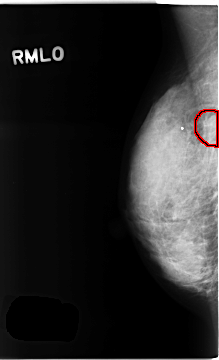

C_0258_1.RIGHT_MLO

RIGHT_MLO LINES 4672 PIXELS_PER_LINE 2840 BITS_PER_PIXEL 12 RESOLUTION 50 OVERLAY

FILE: C_0258_1.RIGHT_MLO.OVERLAY

TOTAL_ABNORMALITIES 1

ABNORMALITY 1

LESION_TYPE MASS SHAPE OVAL MARGINS OBSCURED

ASSESSMENT 4

SUBTLETY 4

PATHOLOGY BENIGN

TOTAL_OUTLINES 1

BOUNDARY